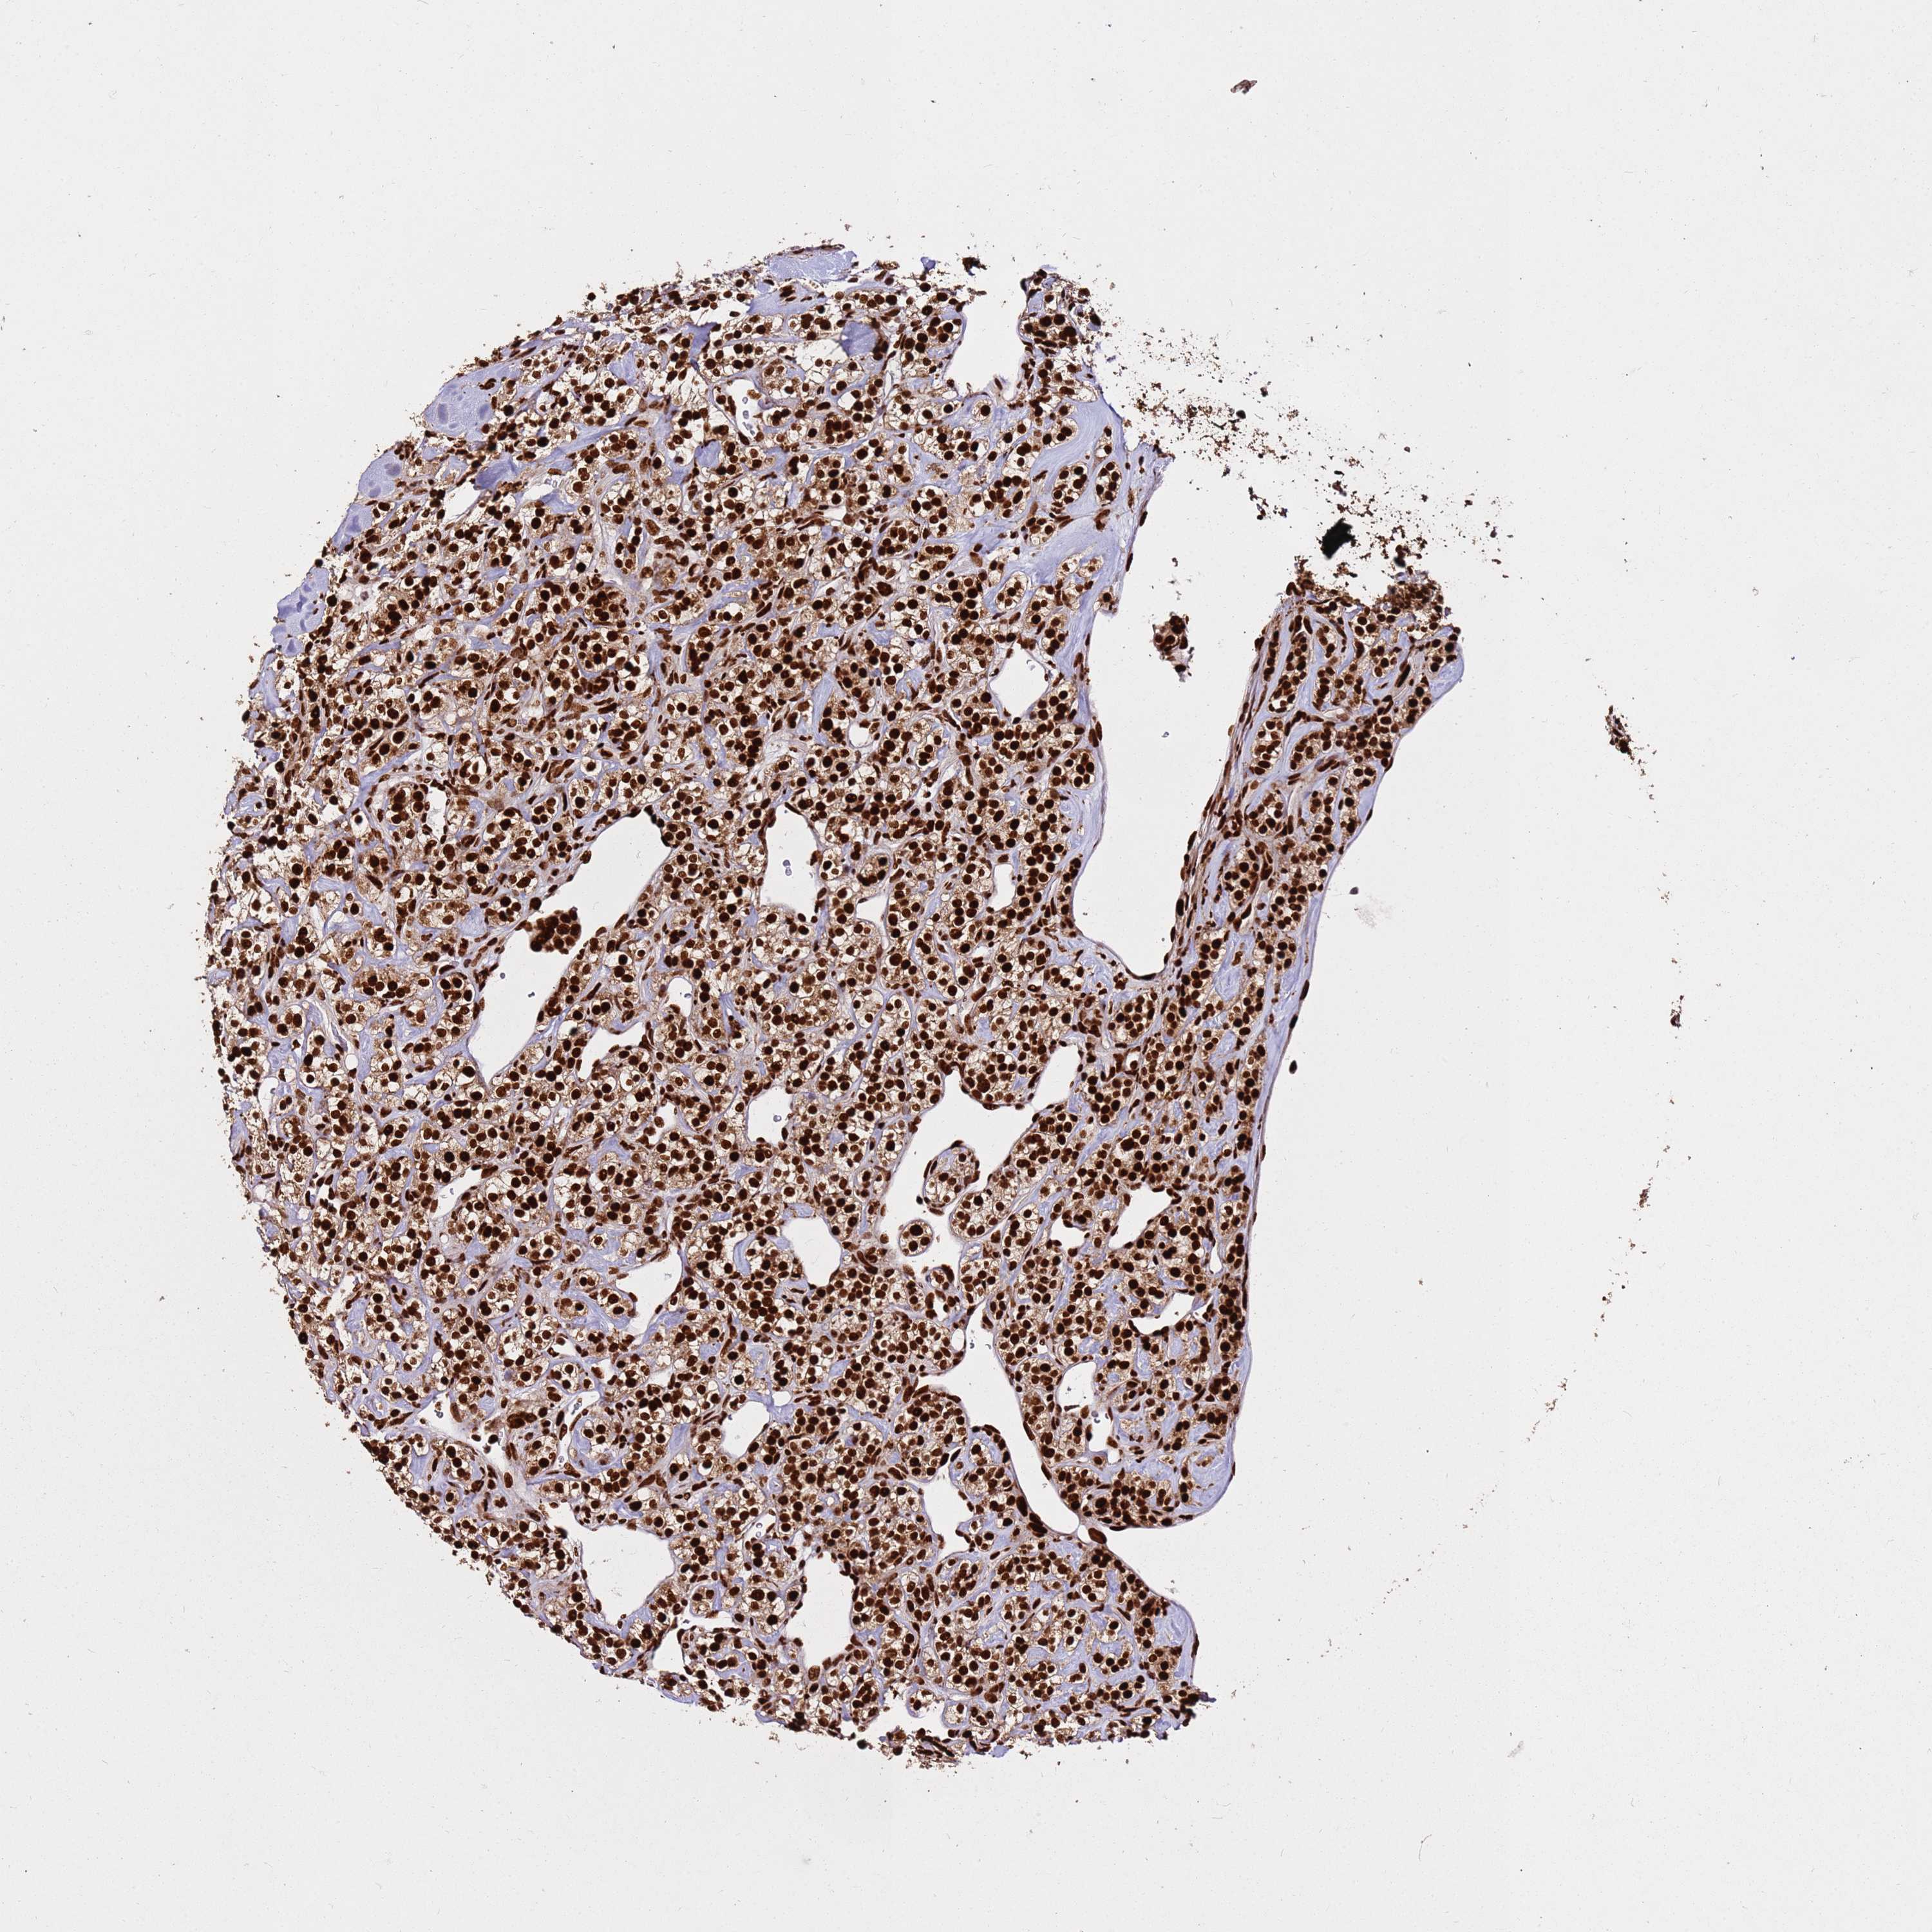

HNRNPAB is not prognostic in Kidney Renal Clear Cell Carcinoma (validation)

Average pTPM 123.4

Number of samples 100